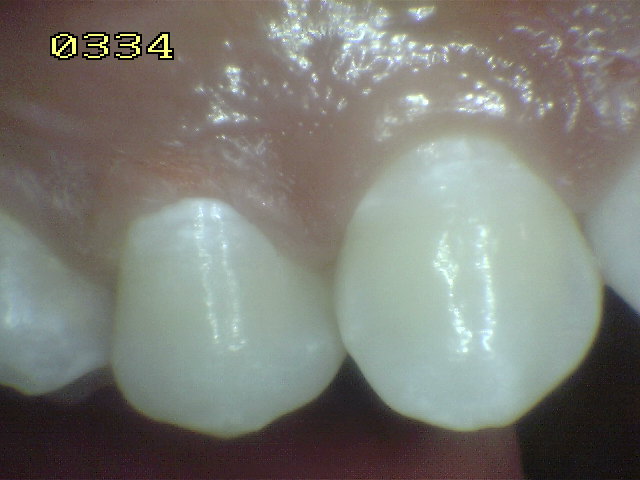

Casos clínicos de fluorosis leve.

Esmalte liso, traslúcido y cristalino acompañado con gruesas líneas horizontales blanquecinas.

Las manchas opacas por fluorosis leve deben diferenciarse con los códigos1 y 2 de ICDAS. En las fluorosis el esmalte aparece brillante; mientras que en el proceso de caries se observa un blanco aspecto de tiza. (sin brillo)